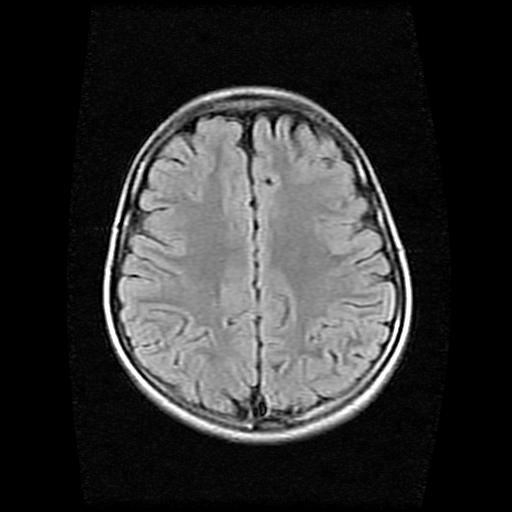

9岁女孩,三岁时诊断为癫痫,一直服丙戊酸钠,现患者一般情况良好,家长复查核磁片,看能否停药..

巨脑回

未见异常信号灶.

停药要结合临床,如无发作可以停。